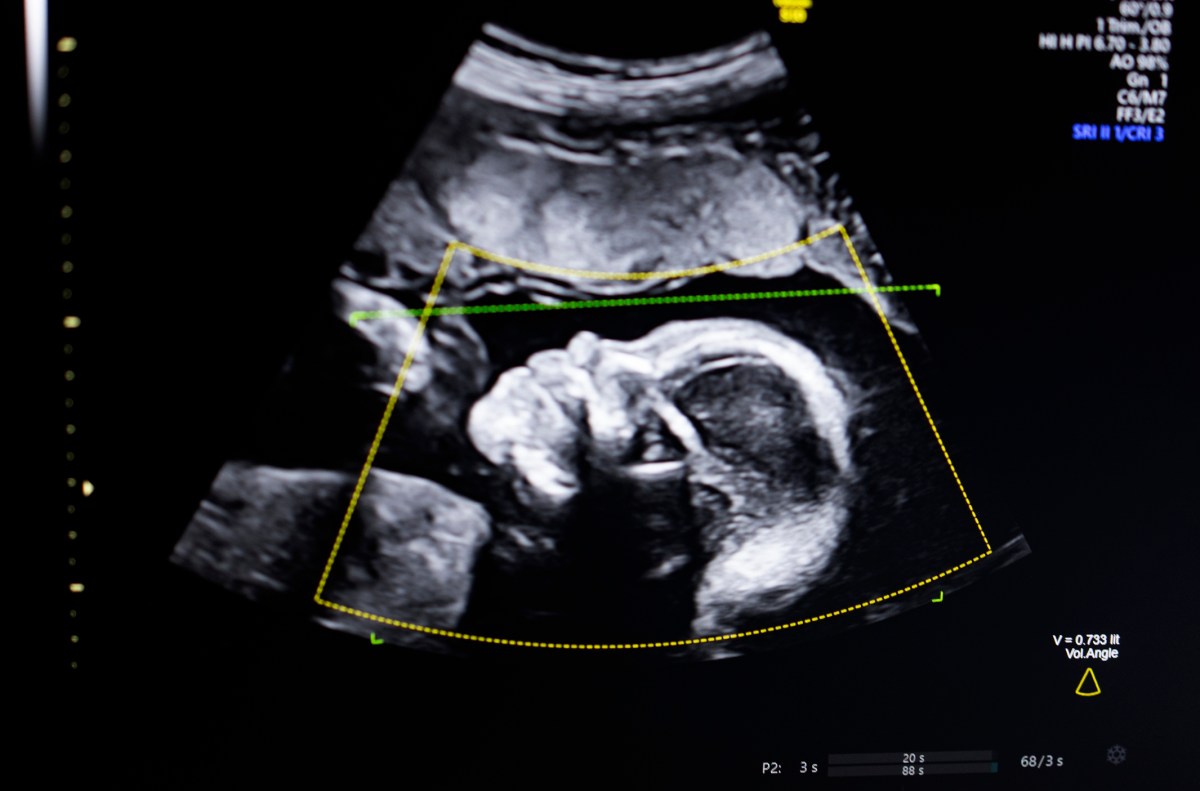

The technology uses computer vision AI “to support fetal ultrasound quality assessment, anatomical completeness, automated reporting, and seamless integration into clinical workflows,” Bustami told TechCrunch.

Bustami said that the prenatal ultrasound has become the “cornerstone” of monitoring pregnancies, but its low-quality images can lead to misdiagnosis.

Bustami said the hardest part was not building his AI models, which were trained on a diverse set of 11,000 ultrasounds, but ensuring the tech performed reliably in the real world, especially on demographics with the highest risk for a tragic outcome.